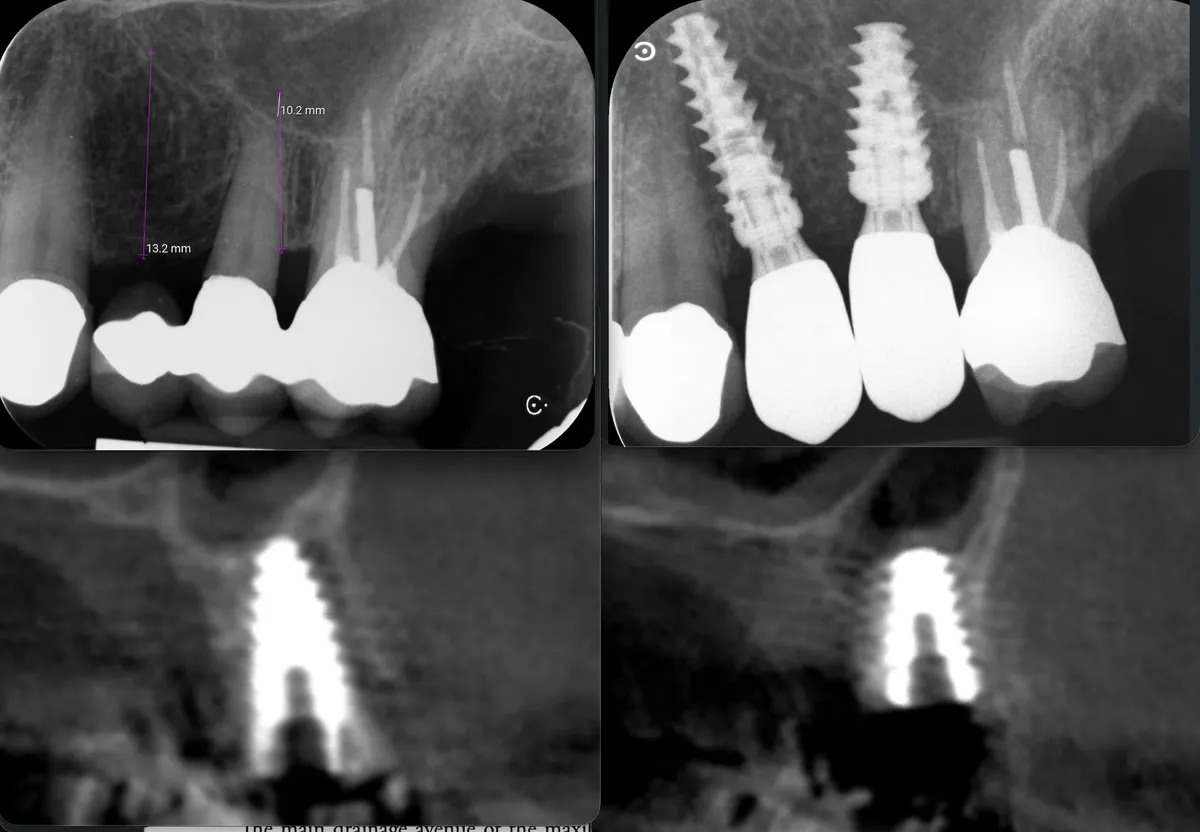

Cresta atrofica in zona 4.6 con difetto osteo-mucoso e cheratinizzata quasi assente: Bonebending 4.0 e impianto in unica seduta. Risultato a 3 mesi.